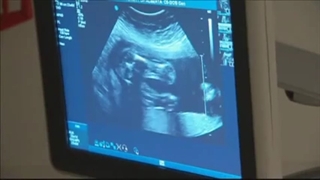

پخش صدا بارداری بعد از 4 سال اشتراکگذاری لیست پخش ۰ نظر ۰ نظر دانلود دانلود ویدیو دانلود کیفیت 480p ۴.۴۷ مگابایت دانلود کیفیت 360p ۲.۹۸ مگابایت دانلود کیفیت 240p ۱.۸۴ مگابایت دانلود کیفیت 144p ۱.۱۵ مگابایت گزارش تخلف بیشتر گزینههای بیشتر لیست پخش لایکها گزارش تخلف ۰ لایک دکتر اکرم مهدیزاده شاهی منتشر شده در تاریخ ۱۴۰۰/۱۰/۳۰ این کانال دنبال شد دنبال کردهاید دنبال کردن این کانال دنبال کردن سونوگرافی جنین ۷ هفته ای برای خانمی که بعد از ۴ سال باردار شدند توسط دکتر اکرم مهدی زاده ادامه نظرات لبخند لبخند لغو ثبت نظری برای نمایش وجود ندارد.